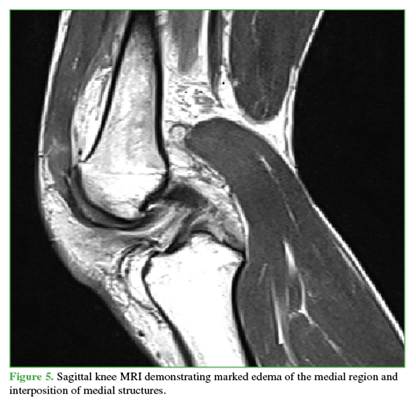

A 27-year-old male farmer residing in a rural area, with no relevant medical history, suffered a traffic accident after falling into a ravine while riding a motorcycle, resulting in trauma to his right shoulder and knee. He initially sought care at a rural hospital, where marked edema, ecchymosis, and a positive dimple sign were identified in the right knee. He also had limited range of motion in both the shoulder and the knee. As X-rays were not available, he was referred to a hospital with orthopedic services. There, initial radiographs were obtained (Figures 1 and 2), documenting a diaphyseal humeral fracture that was immobilized with a sugartong splint. In addition, a posterolateral knee dislocation and a lateral patellar dislocation were diagnosed. Two orthopedic surgeons attempted three reductions under sedation (no anesthesia was available), successfully reducing the patella but not the knee. It was decided that the patient required transfer to a trauma center for urgent open reduction and to rule out an associated vascular injury. The knee was immobilized with a bivalved hip-to-foot splint and he was referred.

Radiographs showed widening of the medial joint space consistent with medial instability. Further imaging was obtained with magnetic resonance imaging (Figures 4 and 5) to evaluate possible interposed tissues or structures, and with CT angiography (Figure 6) to rule out vascular injury given the time elapsed since trauma. Marked edema was noted in the medial soft tissues, including the capsule and medial structures in the intercondylar region, along with persistent knee subluxation. Vascular compromise was ruled out, with preservation of the femoropopliteal vascular bundle.